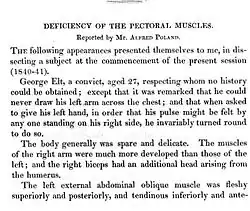

History

It was named in 1962 by Patrick Clarkson, a New Zealand-born British plastic surgeon working at Guy's Hospital and Queen Mary's Hospital, London. He noticed that three of his patients had both a hand deformity and an underdeveloped breast on the same side. He discussed this with his colleague at Guy's Hospital, Dr Philip Evans, who agreed that the syndrome was "not widely appreciated". Clarkson found a reference to a similar deformity published by Alfred Poland, an English surgeon, over a hundred years earlier in Guy's Hospital reports, in 1841.[24] Clarkson was able to find the hand specimen dissected by Poland, which was still held in the hospital pathology museum.

Poland had dissected a convict known as George Elt, who was said to be unable to draw his hand across his chest. Poland noted the chest wall deformity, and this was illustrated in his article. The hand was also dissected and preserved for posterity in Guy's Hospital museum where it remains today. It cannot be truly said that Poland described this syndrome because he only described one isolated case. Clarkson published his series of three cases and named the syndrome after Poland in his article.[25]

- ^ Poland A. (1841). "Deficiency of the pectoral muscles". Guy's Hospital Reports. VI: 191–193. "Plate". Guys Hosp Rep. 1836.